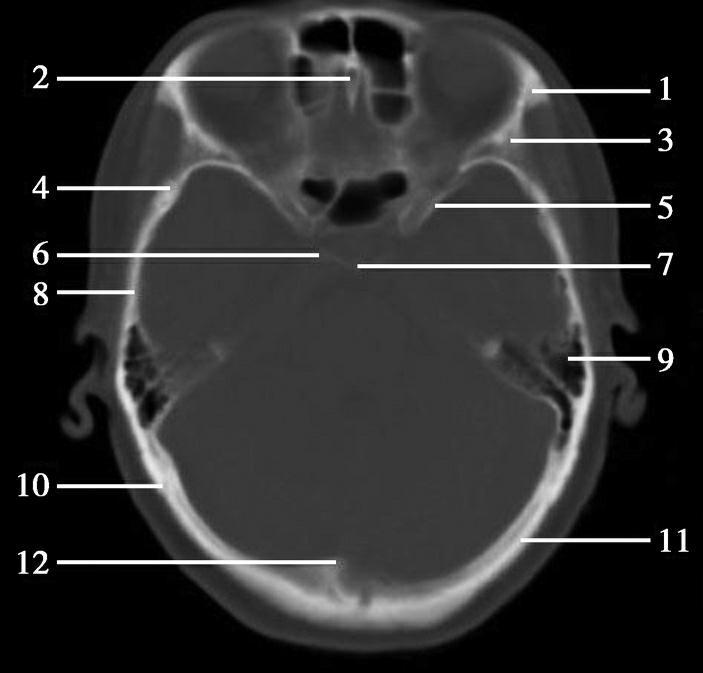

图1-2-2 颅底层面(骨窗)

A.横断面;B.横断面标注

1.鼻骨;2.筛窦纸板;3.颧骨眶突;4.翼腭窝;5.蝶骨大翼;6.卵圆孔;7.破裂孔;8.颞骨颧突;9.棘孔;10.斜坡;11.颞骨岩部;12.乳突;13.颈静脉孔;14.枕乳突缝;15.枕骨;16.枕内隆凸

层面前部呈开口向前的“V”字形,正中为鼻中隔,向两侧依次为筛窦和眼眶,眼眶内前部为眼球,后部为眶脂体。翼腭窝位于眼眶后部,窝内含有脂肪并有上颌神经通过。层面中部为蝶骨体,蝶骨体中部可见含气蝶窦,蝶窦后方为枕骨基底部,两者呈前后关系,其上面构成斜坡。蝶窦两侧为蝶骨大翼,其后外侧缘处由前向后可见卵圆孔和棘孔,分别有下颌神经和脑膜中动脉通过。斜坡外侧、岩骨尖前方为破裂孔。蝶骨大翼与眶外侧壁的颧骨借颧弓相连,颧弓和蝶骨大翼之间有咬肌及颞肌。层面中部外侧为外耳道。颞骨岩部呈“八”字形,相互之间借破裂孔软骨、蝶岩软骨结合和岩枕软骨结合连接。岩部后外侧的乳突部内可见乳突小房,乳突部与枕骨相接。岩骨后部可见颈静脉孔,内有颈内静脉、舌咽神经、迷走神经和副神经通过。层面后部为颅后窝,其内可见延髓,延髓前方为延髓前池,内有椎动脉,后外侧为小脑半球下部,后方为第四脑室、小脑扁桃体及小脑蚓部。

破裂孔、卵圆孔、棘孔及斜坡等均为重要的解剖结构,临床常见疾病如鼻咽癌常侵犯上述结构(图1-2-3)。颈静脉孔区较常见的肿瘤为颈静脉球瘤,常伴有颈静脉孔及其邻近骨质的破坏(图1-2-4)。